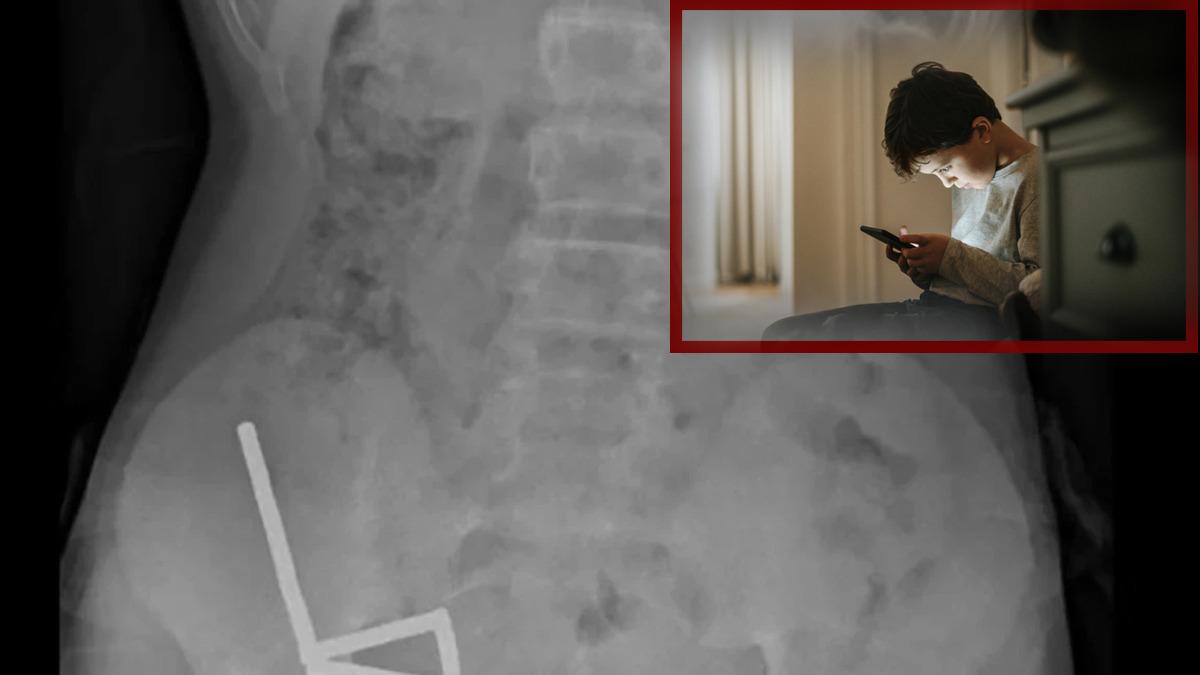

Çekilen röntgen görüntüleri, mıknatısların bağırsaklarda dört ayrı düz çizgi halinde kümelendiğini ve manyetik kuvvetler nedeniyle farklı bağırsak bölümlerinin birbirine yapıştığını ortaya koydu.

Doktorlar, mıknatısların bağırsaklarda ciddi hasara yol açtığını tespit etti. Çocuğun bağırsağının bir bölümü ve mıknatıslar cerrahi müdahaleyle çıkarıldı. Operasyon, tıp literatürüne geçti.